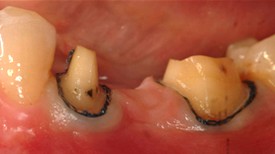

Before: Patient needs Upper Arch Rehabilitation. Presents with Upper Anterior teeth that are stained, incisal edges (tooth edge) are worn down and chipped, and gumline recession is present.

After: Smile restored with placement of 8 Upper All Porcelain Crowns (Caps). Gumline and incisal edges are now uniform. Patient now has longer, better shaped teeth to enhance the smile line and aid in chewing/biting function.